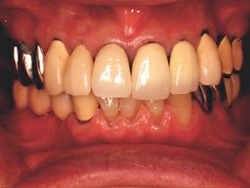

術前口腔内(正面観)

術後口腔内(正面観)もう入れ歯は要らなくなりました。